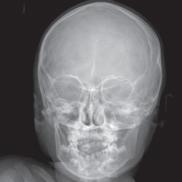

“When using standard MRI approaches, we are limited to brighter and darker shades of gray,” says MIITT co-director, Nicole Seiberlich, PhD, Research Professor of Cardiovascular Imaging and Associate Professor of Radiology. While radiologists are both skilled and experienced at reading and interpreting these images, introduction of a numerical measurement technique eliminates subjectivity, providing readers with specific data. “With our proprietary method, Magnetic Resonance Fingerprinting (MRF), radiologists can acquire quantitative data on multiple important properties simultaneously, which improves the accuracy of the diagnostic information. These quantitative tissue property maps include actual numbers that give experts reproducible and actionable results. It has been evaluated in brain, prostate, liver, cardiac, and musculoskeletal imaging.”

One of the many benefits of utilizing the MRF method as opposed to traditional MRI techniques is that it can be applied across vendors and machines to enable quantitative comparisons. “Before MRF, the shades of gray you received depended on all sorts of factors,” says Tom Griesler, MS, third year BME PhD candidate, whose research interests include MRF sequence design and optimization for brain and abdominal imaging. Results varied based on the series, settings, and manufacturer. Using MR Fingerprinting, numerical physical parameters enable comparison across time and space.